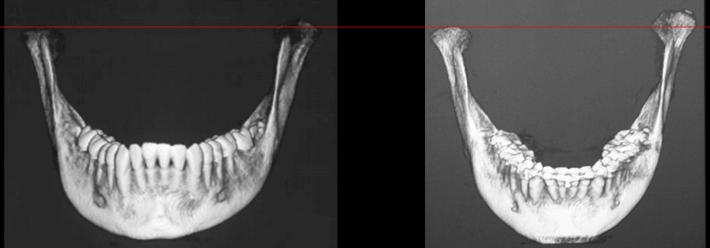

Tomografía Cone Beam Inicial

Evidencia tomográfica de la rápida evolución de la hiperplasia condilar